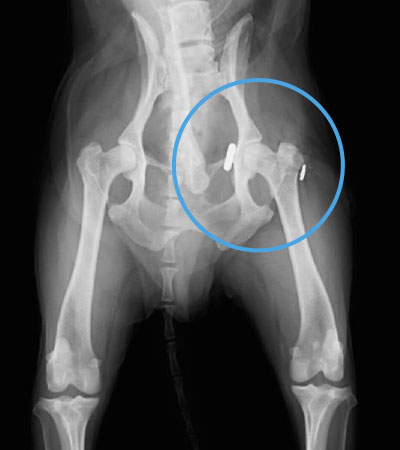

整復(術後)

大腿骨頭が寛骨臼のカップに元通り収まっています